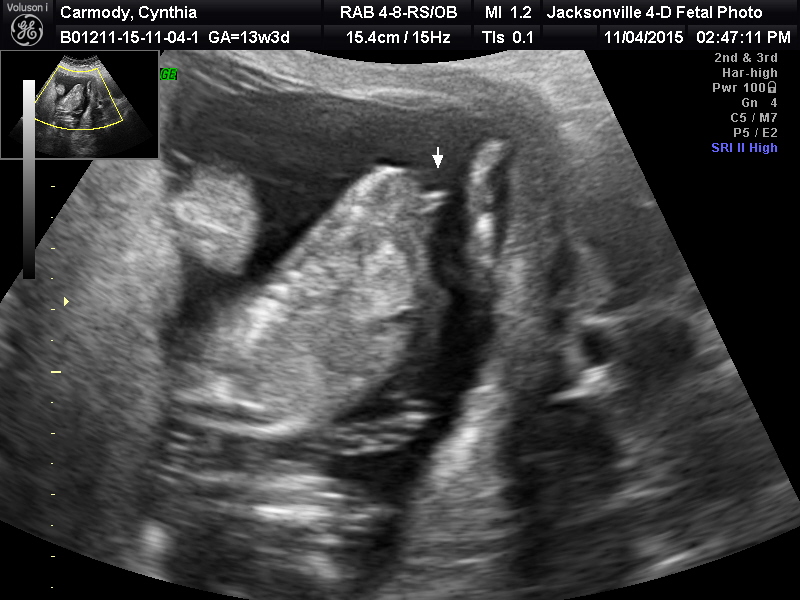

I know I accidentally posted this in the wrong section. First time using this site, I didn't know how to delete it. But can you tell the gender with the pics posted?